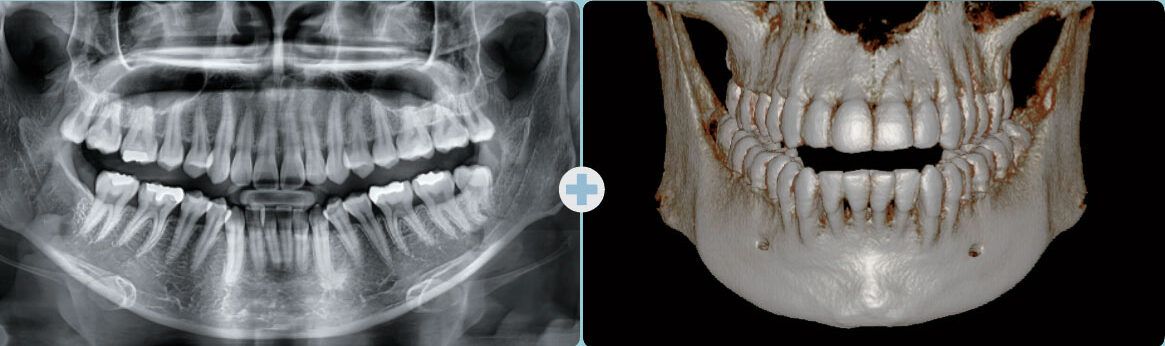

Radiografías Panorámicas.

Tac dental 3D o CBCT.

Radiografía panorámica

TAC de cráneo (Cone Beam)